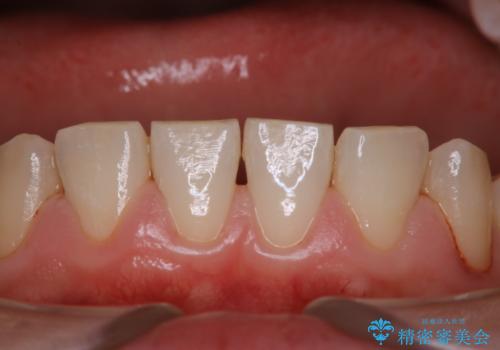

歯周病の治療前にまずはモチベーションUPにPMTCでステインの除去

担当医 歯科衛生士